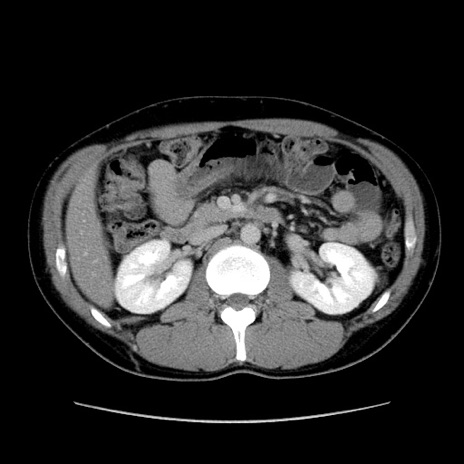

症例36(横断像)

【症例】20歳代 男性

【主訴】心窩部痛

【現病歴】今朝より上腹部痛あり。一旦軽快していたが再度出現したため救急要請。昨日夕に白身の魚を含む刺身を食べた。

【身体所見】BP 136/89mmHg、HR 74/min、BT 37.0℃、腹部:膨満、軟、心窩部に圧痛あり。反跳痛なし、筋性防御なし、腸雑音やや亢進あり。

【データ】WBC 17700、CRP 0.48